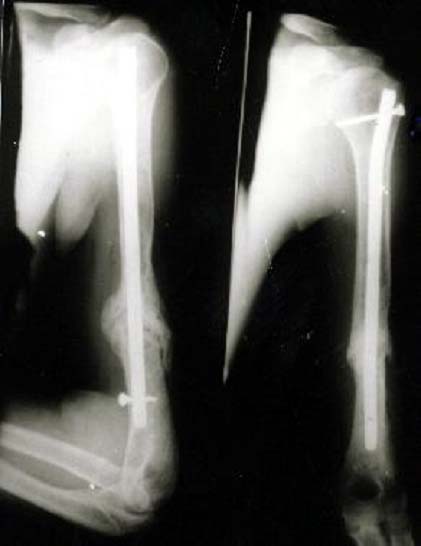

股骨多段粉碎骨折 采用闭合穿钉法,带锁髓内钉内固定